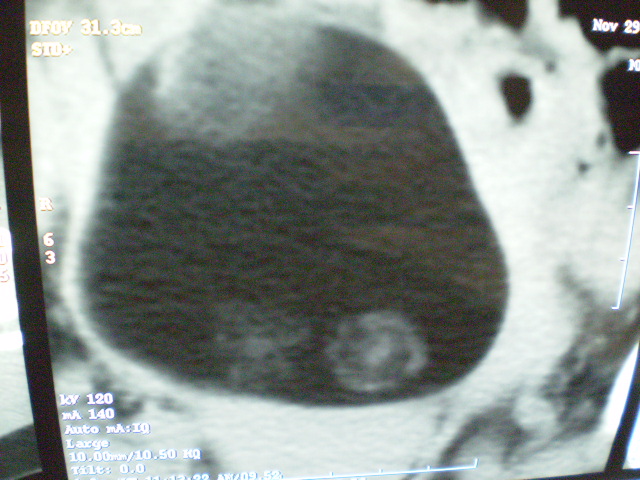

f 60y,b超提示脂肪瘤.[img][/img]

右侧附件囊性畸胎瘤,三种组织均见.

那个高密度灶形状好象牙齿。典型,收藏了

脂肪密度肿块,内可见团块状影,典型皮样囊肿

有钙化,畸胎瘤